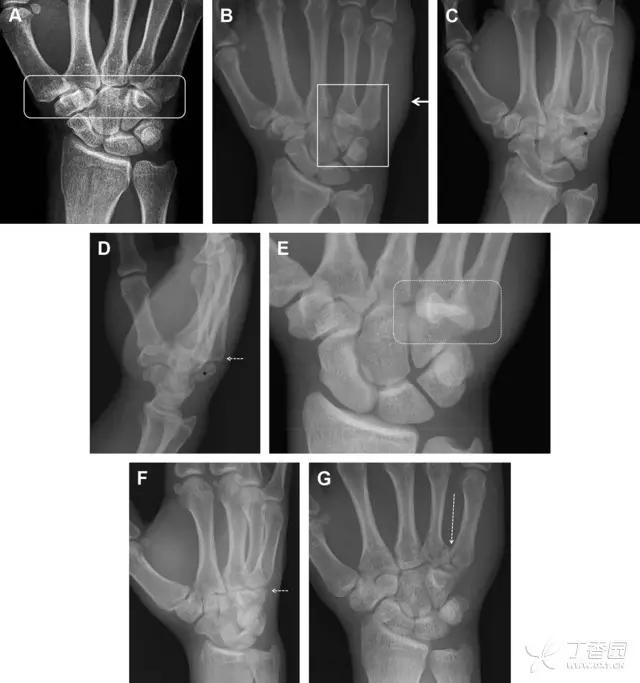

33 腕掌关节骨折脱位

腕掌关节骨折脱位为高能量损伤,常伴有神经损伤。腕掌关节组成骨多,侧位片上重叠遮挡多,骨折不易发现,容易漏诊。在前后位片上,关节面不平滑、关节间隙不对称、关节皮质破坏、关节面重叠常提示腕掌关节骨折脱位。特别是第 4、5 腕掌关节脱位,在前后位片上不容易发现;该损伤不稳定,也称为「变异型拳击手损伤/骨折」。

图 4 第 4、5 腕掌关节骨折脱位。(A)正常腕掌关节,关节面平衡起伏、平行;前后位(B)、斜位(C)、侧位(D),第 5 掌骨近端附近软组织肿胀(白色箭头),冠状面关节面重叠,背侧撞击剪切应力致钩状骨骨折(*),在前后位及斜位片上可见双密度影。第 4 掌骨底部可见微小骨折碎片(D,虚线箭头),第 4、5 掌骨掌侧成角。(E~G)变异型拳击手损伤:第 4、5 掌骨背侧脱位而未见骨折(E,虚线方框),钩状骨有骨折小碎片(F,短虚线箭头),第 4 掌骨基底部关节内骨折(G,长虚线箭头)

34 钩状骨骨折

钩状骨骨折可发生于体部和钩部,钩部骨折更多见,可合并有第 4、5 腕掌关节脱位。受伤机制由直接*力暴**或腕横韧带撕脱伤所致。骨折征象包括钩部无显示、骨皮质边缘模糊、硬化或双密度影等。常规的正侧位常无法明确诊断,需要加拍腕管位,可清晰显示其钩部。

图 5 打高尔夫球后腕部急性疼痛。常规腕关节 X 线片正常(X)。腕管位片(B)隐约可见钩部横行骨折(虚线箭头),CT 检查(C、D)进一步明确了诊断

35 三角骨骨折

三角骨骨折是除舟状骨骨折外腕关节常见的骨折之一。其背侧是背侧桡腕韧带的附着点,因此背侧骨折更常见。常规正侧位片基本可明确诊断。背侧骨折可在侧位片上看到一小骨块。

图 6 三角骨骨折。(A)前后位片骨折不明显,(B)仅在侧位片上见一小骨块(短箭头),伴有软组织肿胀(长箭头)。

36 腕关节不稳定与脆弱区

月骨周围脱位和月骨周围骨折脱位常发生于摔倒后手掌撑地,由过伸、轴向*力暴**所致。所谓的「脆弱区」包括桡骨茎突、大多角骨、舟状骨、头状骨近端、钩状骨近端、三角骨的月骨缘、尺骨茎突。

图 7 经舟状骨骨折月骨周围脱位(腕关节前后位、斜位、侧位)。(A,B)前后位、斜位示月骨腰部骨折(黑箭头),第 1、2 腕弧中断,舟状骨近极(*)仍在原位,而远极(虚线)背侧脱位